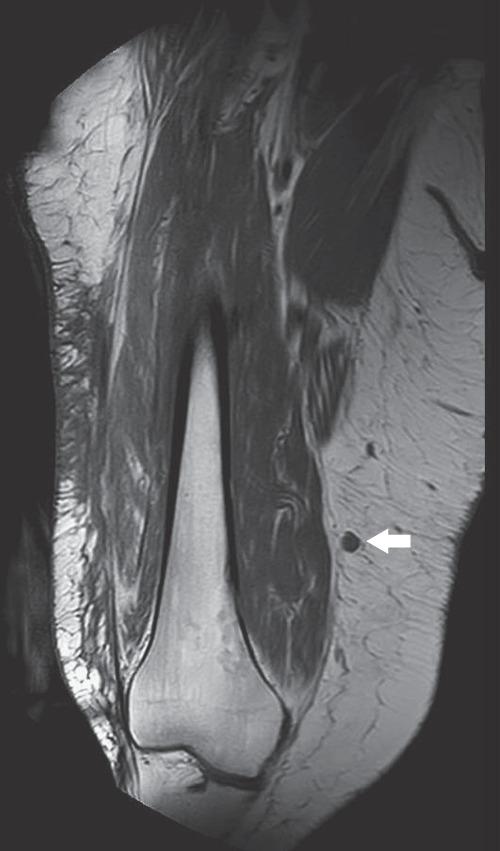

默克尔细胞癌是一种进展迅速的非黑色素瘤皮肤癌,复发风险高。当复发发生时,其预后较差,且缺乏针对此类病例的管理指南。本文描述了一个具有挑战性的病例,其中创新性地使用碘 - 125放射性粒子使我们能够精确识别并切除两个不可触及的复发性结节。由于过去两次切除和两个疗程的放疗后存在瘢痕组织,手术的安全性和准确性受到了影响。放射性粒子定位在乳腺癌中是一种广为人知的操作,显示出在其他癌症类型和复杂临床情况中扩展应用的潜力。

https://cdn.ncbi.nlm.nih.gov/pmc/blobs/9d98/7321529/80d6ca0b1076/CRIS2020-1789185.003.jpg

https://cdn.ncbi.nlm.nih.gov/pmc/blobs/9d98/7321529/930949cba570/CRIS2020-1789185.001.jpg

https://cdn.ncbi.nlm.nih.gov/pmc/blobs/9d98/7321529/e339b5685cc1/CRIS2020-1789185.002.jpg